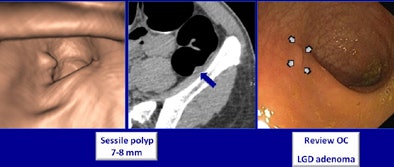

In all, nine patients had areas of nontagged stool (1.8%), and three patients had segments with poor distention (0.6%). All files were successfully transmitted. CTC and optical colonoscopy revealed 88 polyps that were 6 mm or larger in 69 patients, the team found.

Based on results from both exams, including repeated colonoscopy exams when necessary, CTC actually beat out optical colonoscopy in two areas: Sensitivity for detecting adenomas 6 mm and larger was 98% sensitivity for CTC versus 90% for optical colonoscopy, and sensitivity for detecting advanced neoplasia was 100% for CTC versus 91% for colonoscopy. The calculation takes into account six missed lesions plus 14 lesions confirmed at repeat CTC -- 14 of the 20 lesions that colonoscopy missed were in the right colon, where colonoscopy has traditionally done a poorer job.